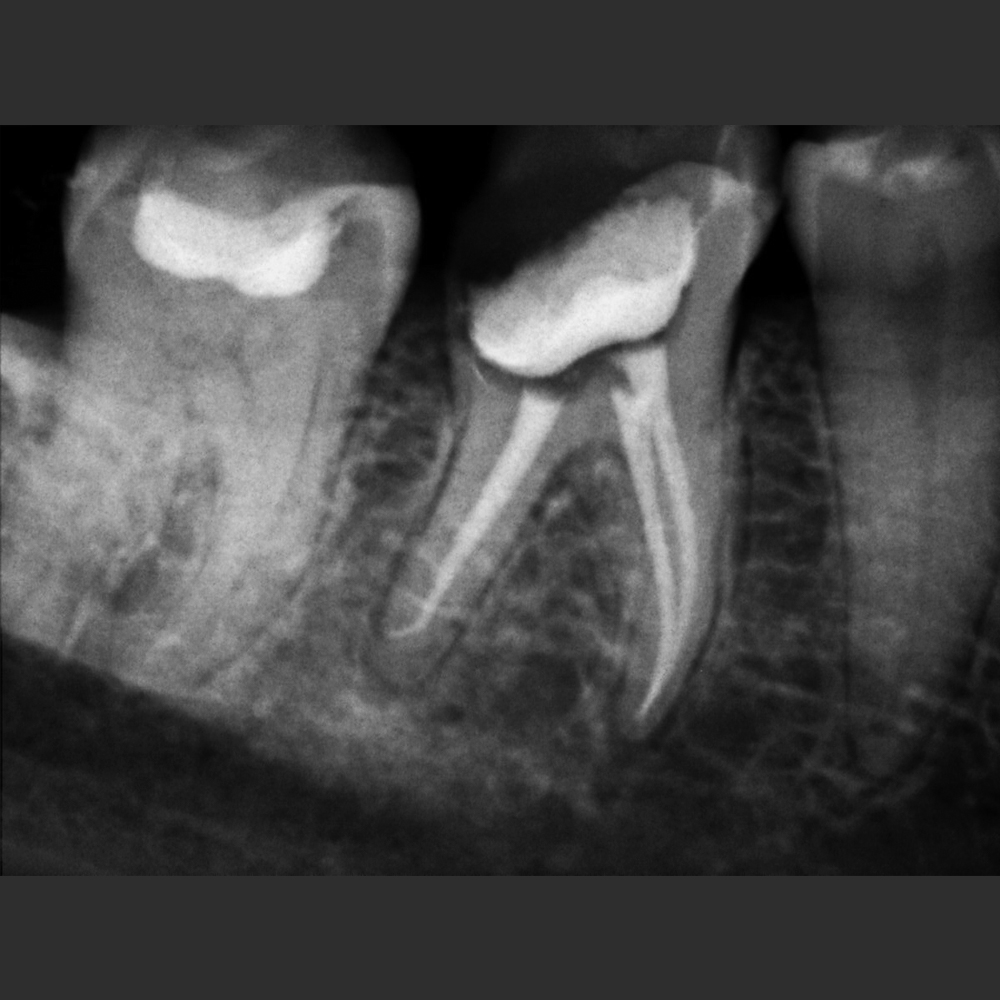

New IDA son los sensores intraorales de la linea New Ida con soluciones eficientes de las imágenes para un diagnóstico nítido, preciso y seguro.

Captura imágenes de alta definición en tiempo real.